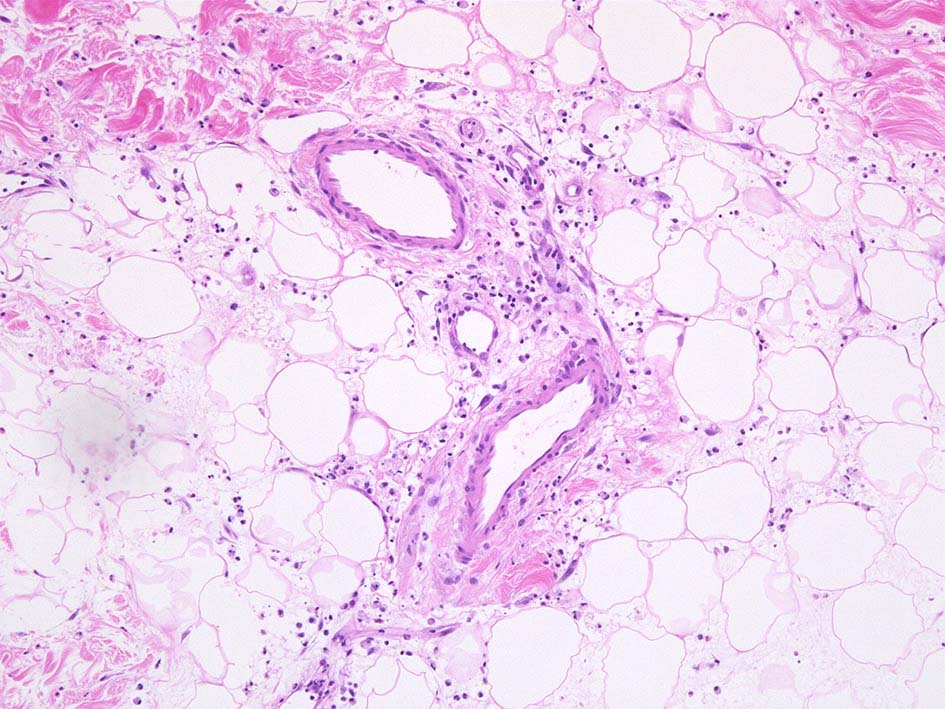

Case02 前胸部皮膚

73 year old male

lt

骨髄異形成症候群で入院中. 発熱, 関節痛に加えて四肢, 胸部など上半身に潰瘍形成をともなう浮腫性紅斑が出現してきた. 皮下硬結あり. Sweet症候群と診断.

中央に黒色痂皮を示す紅斑. 硬結の強い部位から生検される.

HE x40. 表皮下水疱あり. 真皮上層は浮腫状. 真皮から皮下組織にかけて, 多数の好中球が浸潤している. リンパ球, 好酸球が混在, 核破砕物を貪食するマクロファージが増加. 膠原線維にはところどころ変性が見られる.

真皮上層には核破砕物が多く, 好中球浸潤が認められる. 慢性炎症性細胞も浸潤している.

フィブリノイド壊死を呈する血管炎は認められない.

皮下脂肪織炎病変には局所的なhemophagocytosisが認められる. 血管にはfibrinoid necrosisは見られない。